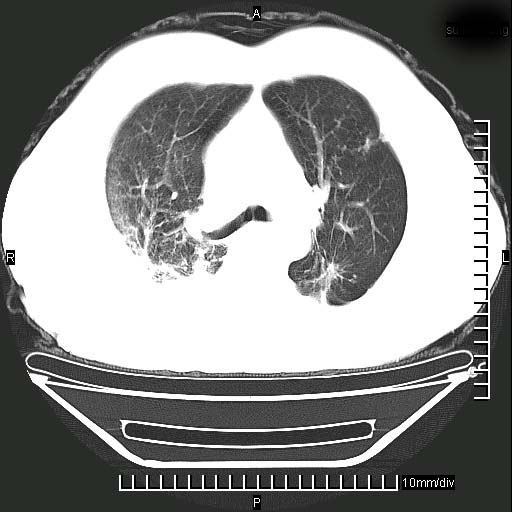

标题: CT24043:胸部增强:男性,60岁

既往肺结核,近10几天,咳嗽,咳痰,右侧胸痛,疼痛较明显,右上肺斑块考虑结核灶胸膜粘连,增强,可惜动脉期没有定好,未见强化,可延迟4分后又见较明显强化,中心见低密度影,如果说结核是边缘强化,可这个灶强化的面积挺大的,让人很挠头。

动脉期